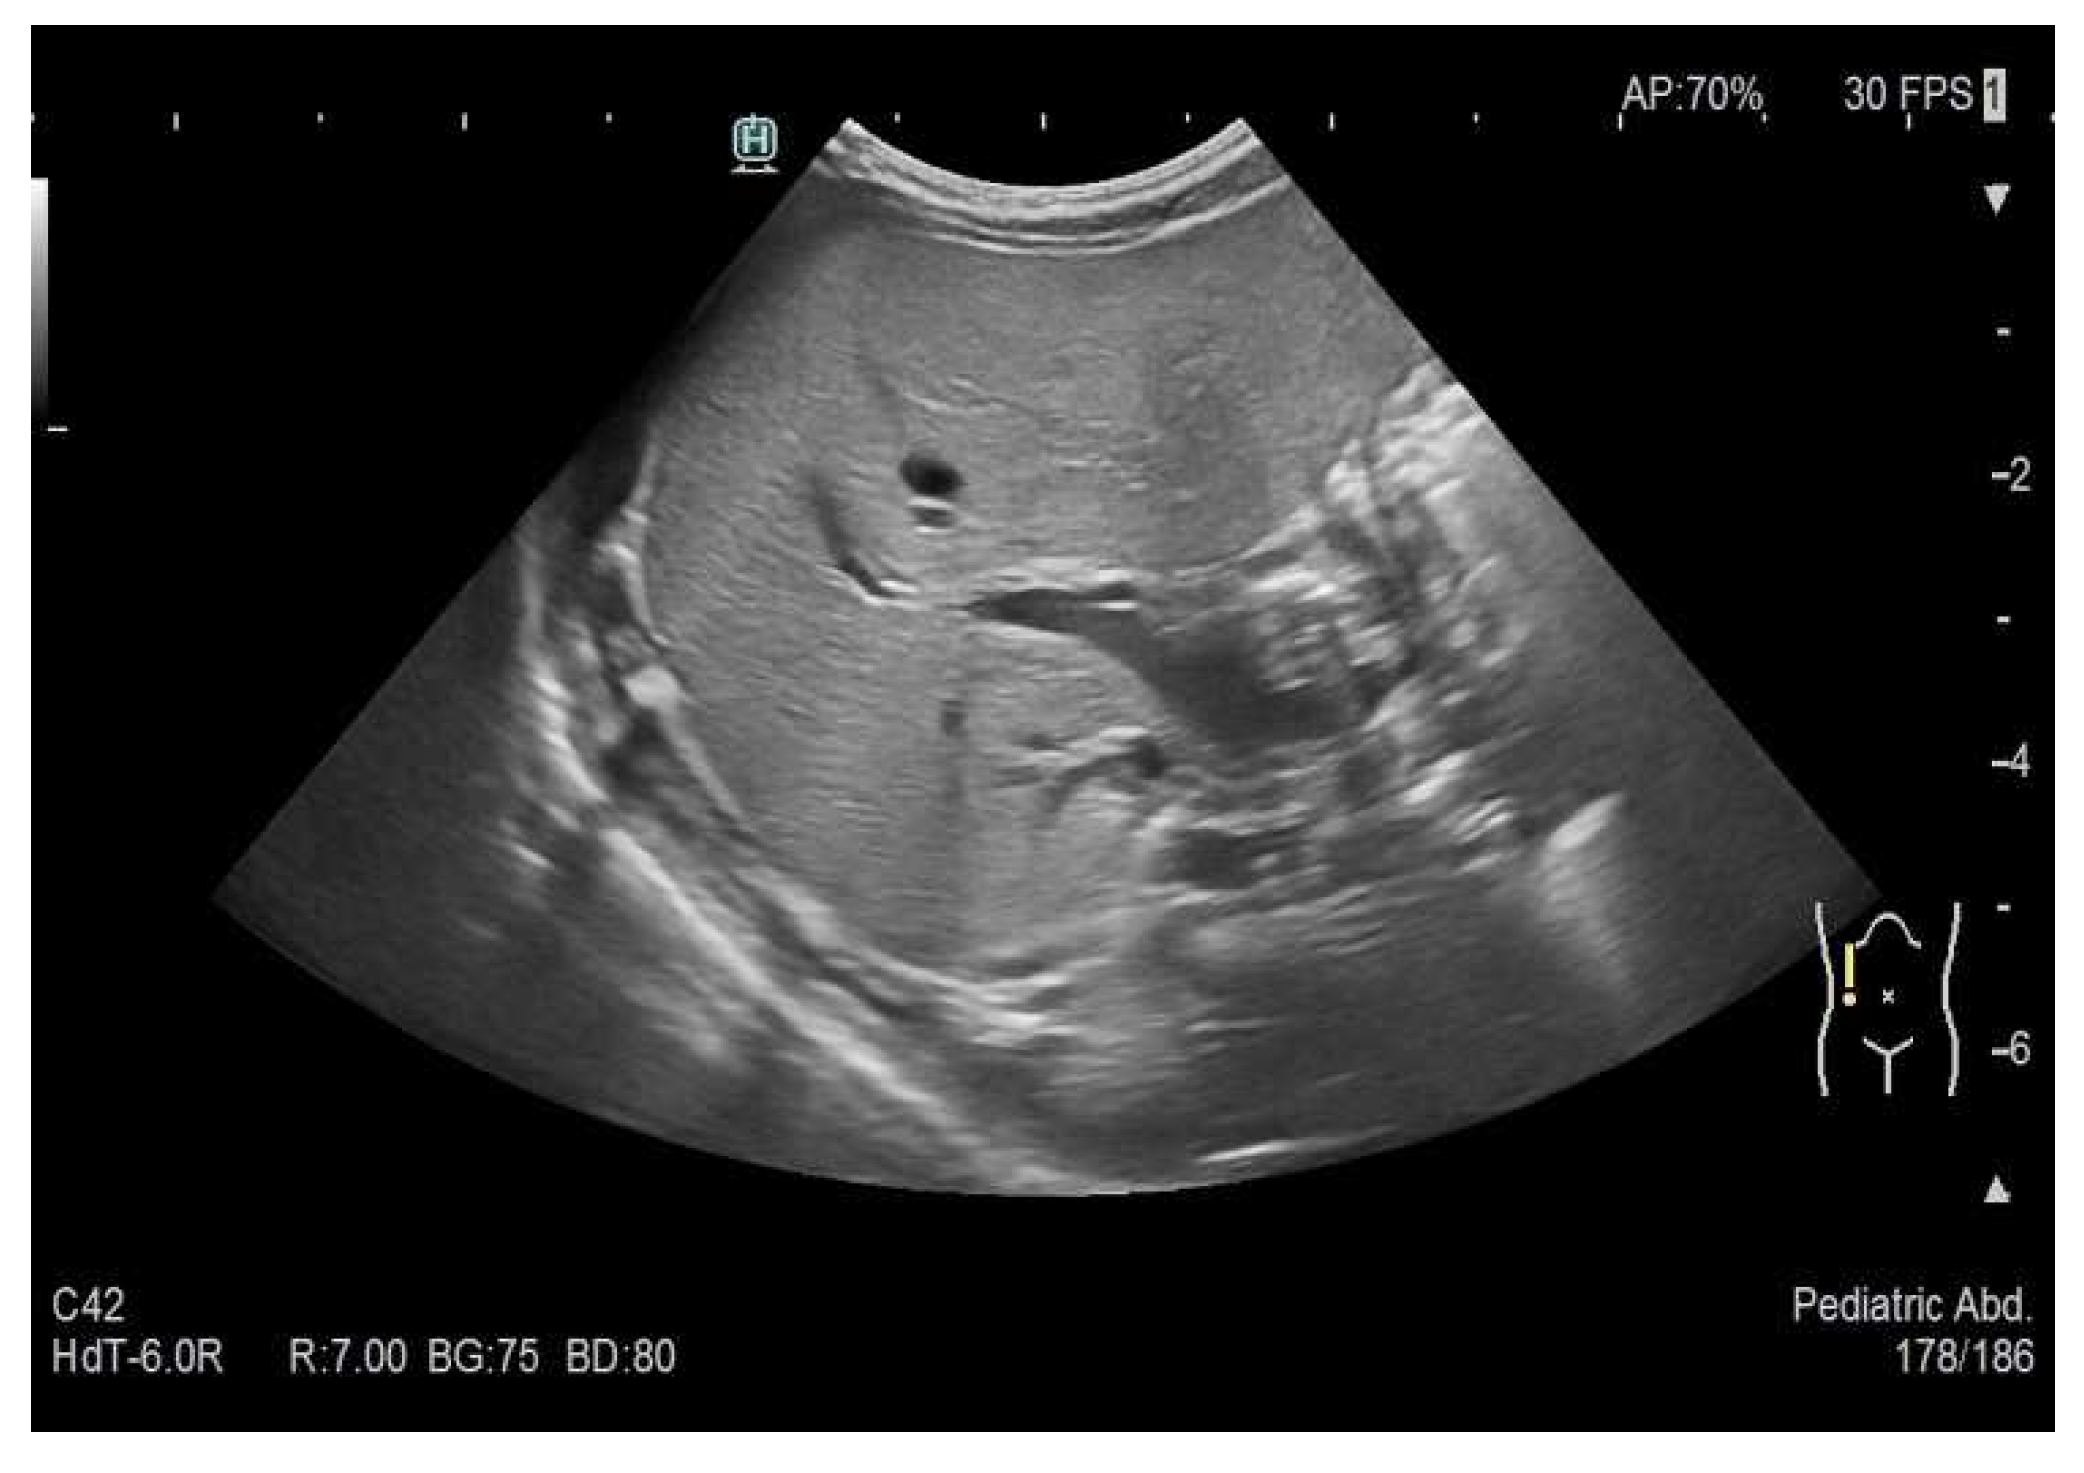

Figure 4. Multiple hypoechoic liver lesions of up to approximately 12 mm in size.

Preprints 73814 g003

Preprints 73814 g002